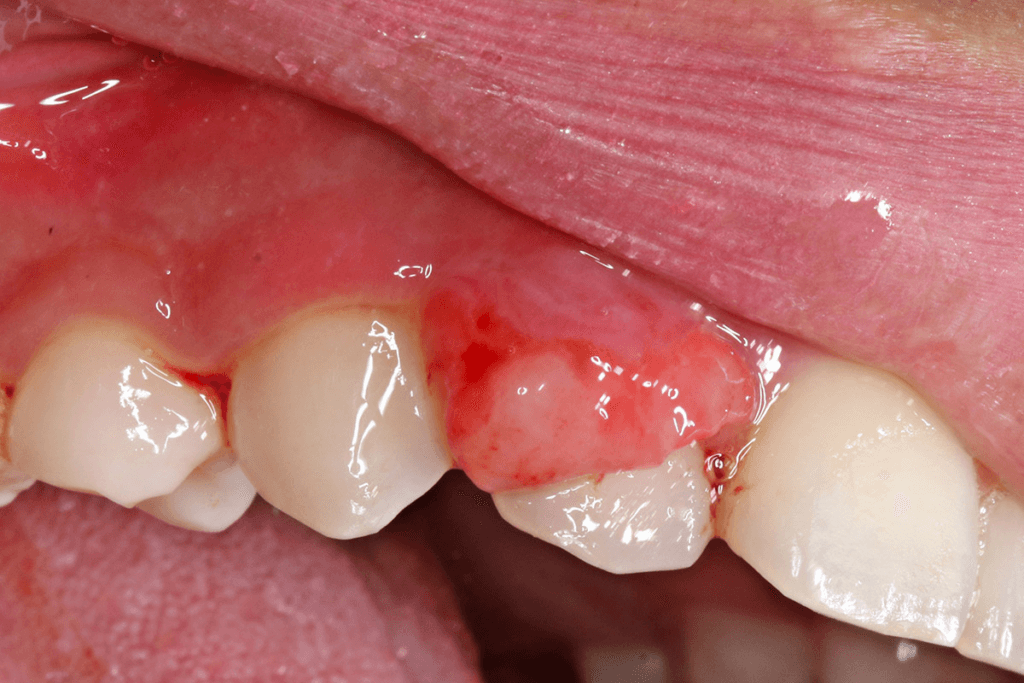

A gingival tumor is an abnormal growth that develops on the gums and can vary widely in nature, size, and its potential impact on oral health. These tumors may be benign (noncancerous) or malignant (cancerous), and their appearance can range from small nodules to larger, more aggressive masses.Gingival tumors require prompt attention and proper diagnosis to ensure appropriate treatment and management. Regular dental checkups and maintaining good oral hygiene are essential for early detection and prevention of possible complications. If you notice any unusual growths or changes in your gums, it is crucial to consult a doctor or dentist.

The symptoms of a gingival tumor can differ depending on the type of tumor and how far it has progressed. Common symptoms associated with gingival tumors include:1. Swelling or a lump 2. Color changes in the gums 3. Gum bleeding 4. Pain or discomfort 5. Pus or discharge 6. Changes in the bite 7. Loose teeth 8. Bad breath (halitosis)